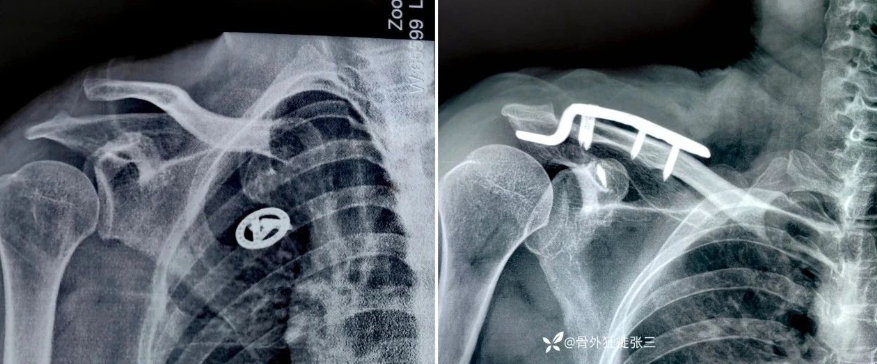

对于踝关节骨折,通常使用腰麻/腰硬联合麻醉(图1)。对于2~4 h的手术,蛛网膜下腔阻滞能很好地满足手术需要。局麻药物选择罗哌卡因10~15 mg或布比卡因10~15 mg,控制麻醉镇痛平面在T10。对于年龄较大,心肺贮备功能较差的患者,可适当减少局麻药用量,同时添加适量阿片类药物(舒芬太尼3~5 μg或芬太尼20~30 μg)来延长镇痛时间,同时也有助于循环的稳定。对于复杂的踝关节骨折手术,可以采用腰硬联合麻醉以保证足够长的麻醉时间。

全身麻醉可以完成任何一种手术,但是对于踝关节骨折手术,很少使用单一的全身麻醉。原因是踝关节骨折复位内固定术后疼痛剧烈,而该类疼痛使用全身系统性用药控制往往效果不佳[39]。如果患者存在椎管内麻醉禁忌,可在全身麻醉基础上配合外周神经阻滞(图1)。